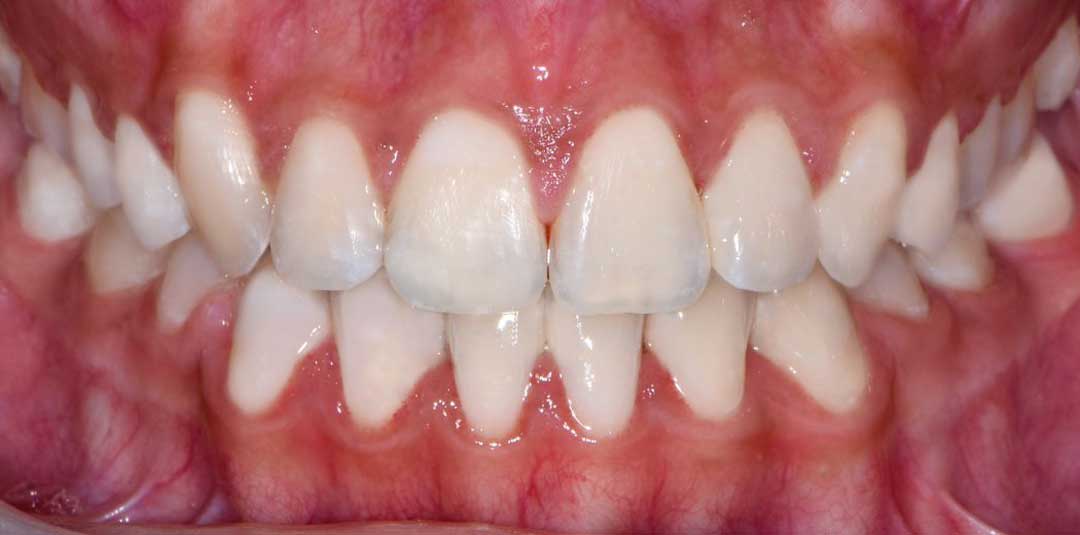

Beautiful Smiles

by Dr. Paolo Bellini